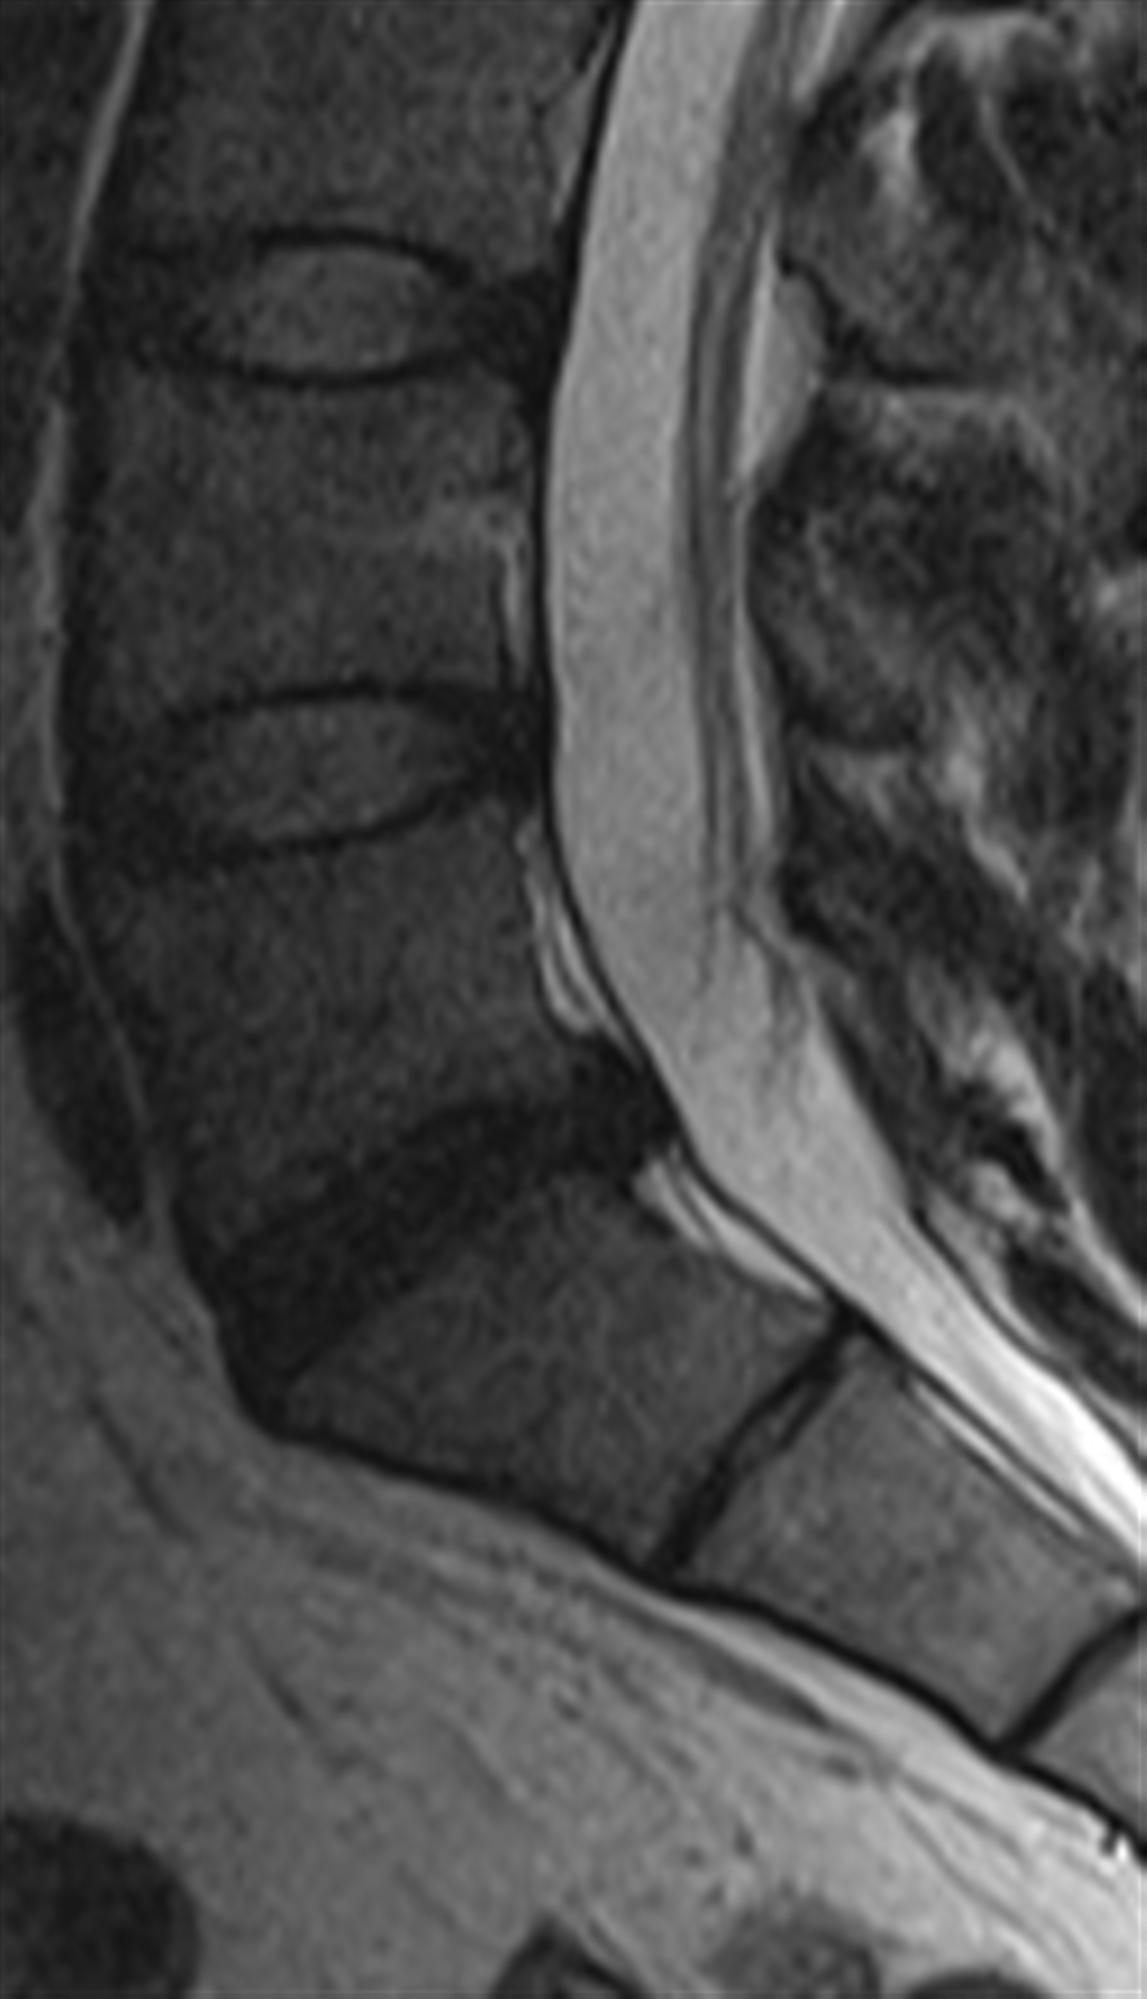

Lumbar Disc Herniation (a) Showing herniated disc at L4/L5 level [14 Lumbar Disc Herniation Orthobullets Approximately 95% of disc herniations in the lumbar. Direction of herniation (e.g., posterolateral vs. On physical exam, no saddle anesthesia, muscle weakness, or sensory changes are noted. Cervical) may change the nerve root that is compressed common disc. Due to the vertical anatomy of a lumbar nerve root, a paracentral and foraminal disc herniation will affect different nerve roots Among. Lumbar Disc Herniation Orthobullets.

Herniated Lumbar Disc Mri Lumbar Disc Herniation Orthobullets Due to the vertical anatomy of a lumbar nerve root, a paracentral and foraminal disc herniation will affect different nerve roots Direction of herniation (e.g., posterolateral vs. Approximately 95% of disc herniations in the lumbar. Cervical) may change the nerve root that is compressed common disc. Among the many differential diagnoses of lbp, degenerative disc disease and lumbar disc herniation. Lumbar Disc Herniation Orthobullets.